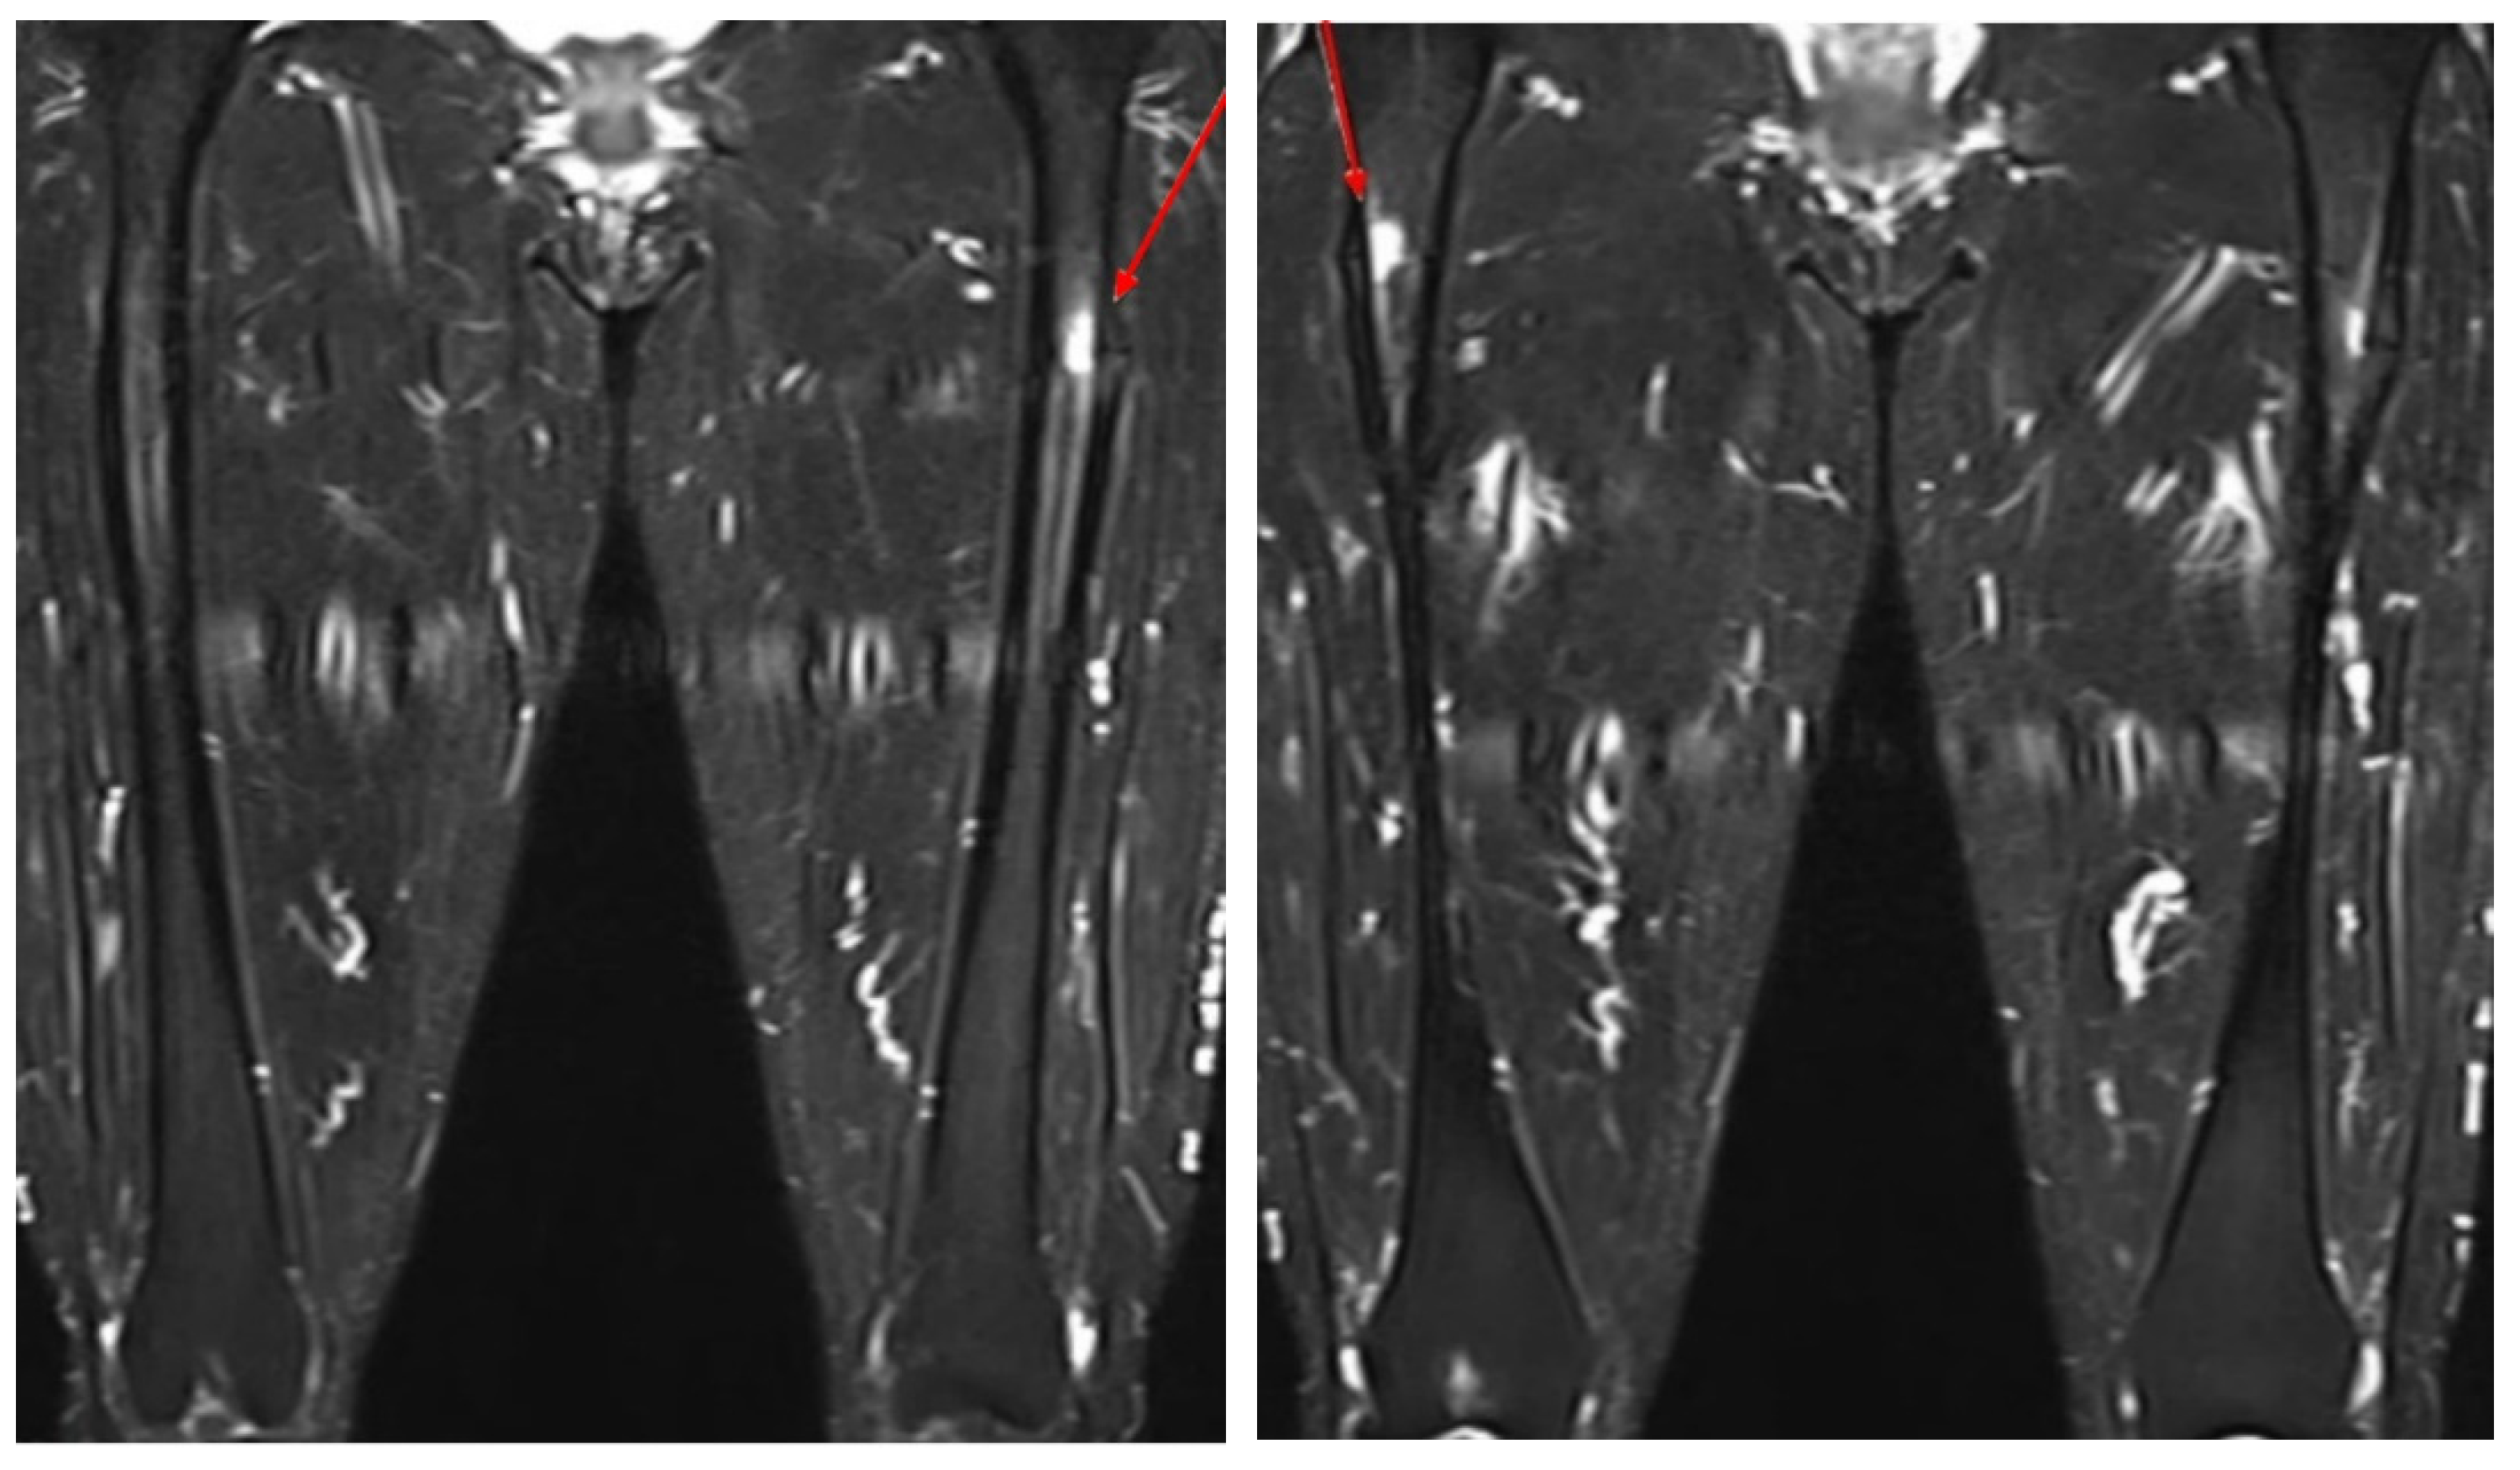

- Kim, J.E.; Yun, M.; Lim, S.-K.; Rhee, Y. Concurrent bisphosphonate-related bilateral atypical subtrochanteric fractures and osteonecrosis of the jaw on bone scintigraphy. Clin. Nucl. Med. 2015, 40, 450–452. [Google Scholar] [CrossRef]